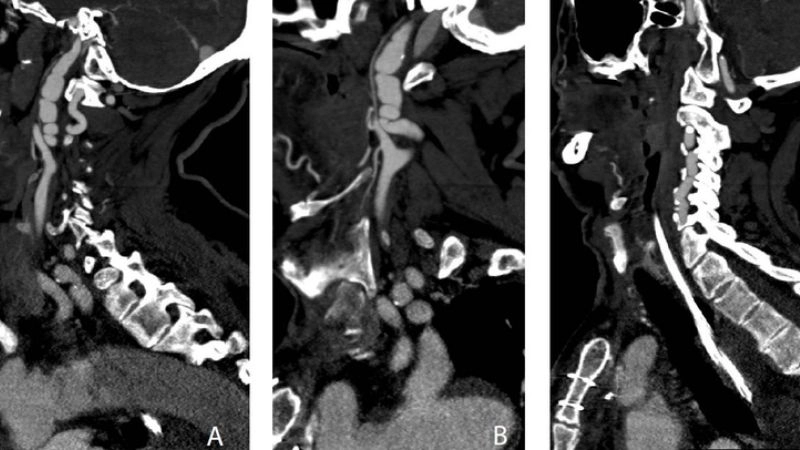

Images visual examples of Fibromuscular Dysplasia

Visual examples of Fibromuscular Dysplasia (FMD) typically highlight twisted arteries or a “string of beads” appearance in imaging scans.